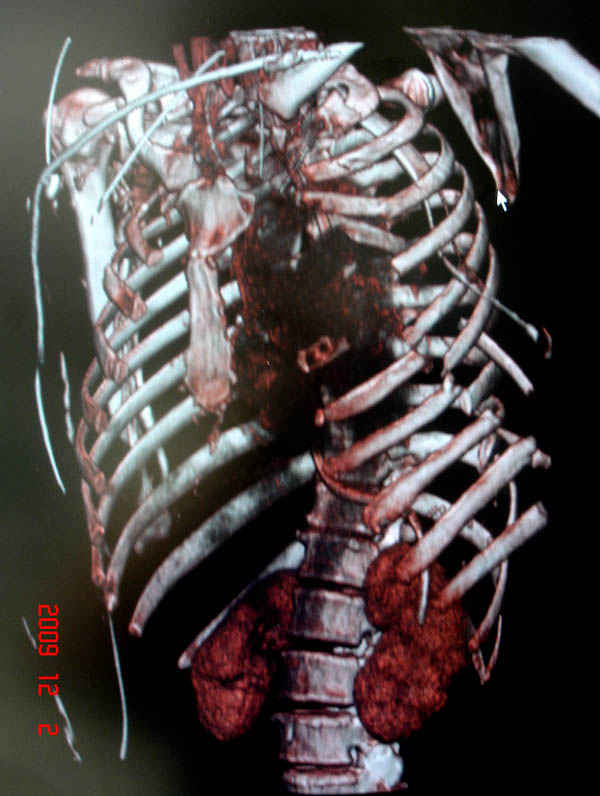

К нам поступила больная 56 лет после автоаварии в бессознательном состоянии, которая срочно заинтубирована в приемном отделении и сделаны необходимые исследования. Данные КТ и рентген показали перелом дистального бедра и Dissociation upper extremity - закрытый отрыв левой верхней конечности на уровне грудинно-ключичного сочленения и множественные переломы ребер.

На поверхности грудной клетки из-за полного разрыва грудной мышцы под кожей заметно биение сердца и след от ремня безопасности. Грудная клетка расширена из-за смещения верхней конечности вверх и латерально. Признаков васкулярного повреждения нет, и из-за отсутствия сознания не смогли определить наличия повреждения нервов.

На седьмые сутки нами совместно с торакальным хирургом сделана операция по фиксации грудинно-ключичного сочленения и переломов ребер.

После кожного разреза обнаружили полный разрыв грудной мышцы и повреждение перикард от уровня второго до восьмого ребер. Хирург находился с нами и после нашей работы зафиксировал повреждение перикарда и разрыв грудной мышцы.

Не все переломы ребра фиксированы, и поэтому хотели услышать комментарии тех, у кого имеется опыт.